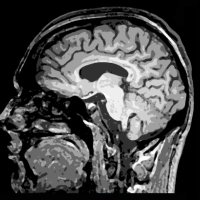

A documentary about recovery from Traumatic Brain Injury - exploring the realities & diversity of a healing brain.